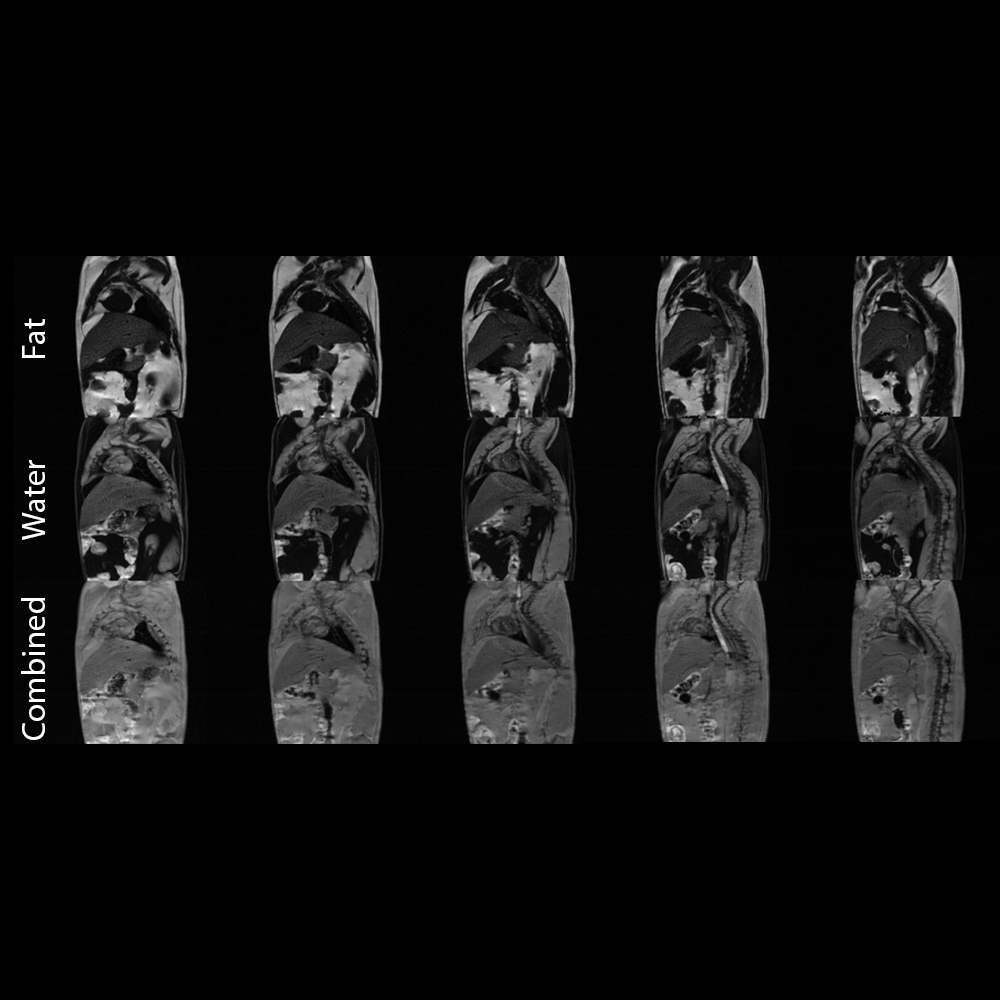

脂肪-水成像

基于多回波梯度回波序列的脂肪与水分分离技术

〉动物模型:Wistar大鼠

〉序列 多回波梯度回波成像: 矩阵尺寸:256×256; 视野范围:70毫米×50毫米;层厚:1毫米; NEX值:2;采集时间:10分钟。

〉线圈:72毫米的发射/接收用音圈